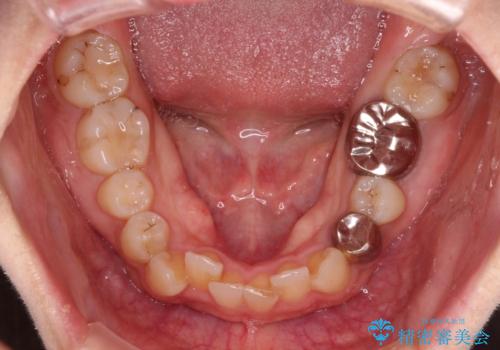

- 前歯のデコボコと深い咬み込みを気にして来院された患者様です。

インビザラインを用いて、前歯の叢生を解消するとともに、深い咬み合わせ(ディープバイト)を改善していくこととしました。

奥歯を後方に直立させることで深い咬み合わせを改善を図り、隠れていた下顎前歯が見えるほどになりました。